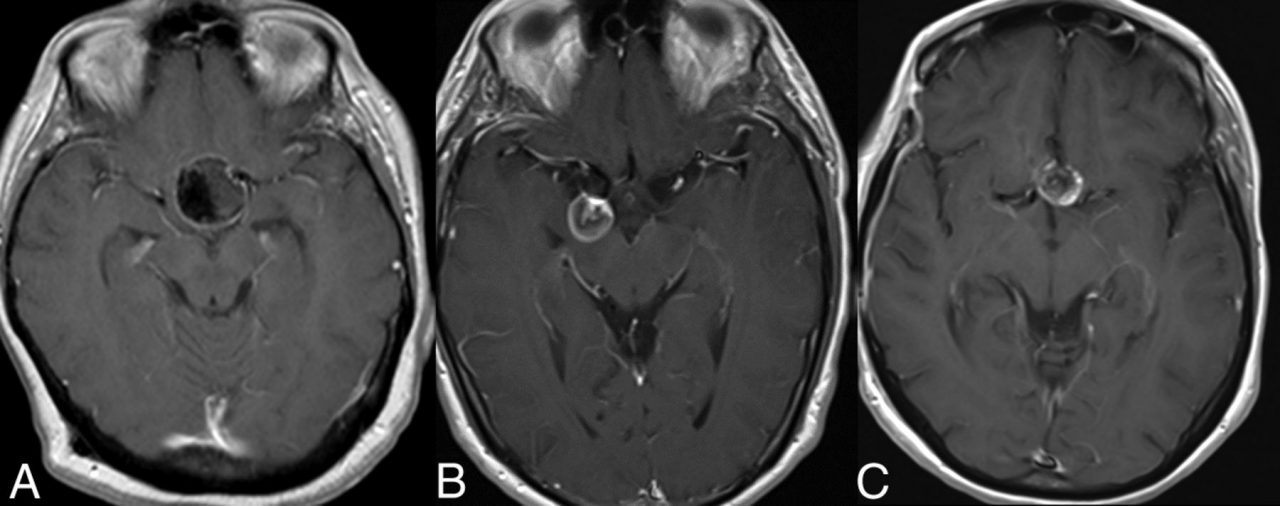

Dural arteriovenöz fistüller (Dural AVF’ler), beyni saran ve dura denen tabaka yüzeyindeki arterler (atardamar) ile venler (toplar damar) arasındaki anormal bağlantılardır (fistüller). Yer yer yumak tarzında düzensiz anormal damarlar eşlik eder. Dural arteriovenöz malformasyon olarak da isimledirilirler.

Dural AVF’ler klinik olarak oldukça değişkendirler. Spontan kürden ölümcül kanamalara kadar değişen klinik gidiş gösterebilirler. Sıklıkla pulsatil tinnitus, tril, kranyal sinir felçlikleri, göz semptomları, kafa içi basınç artışı ile ilişkili olarak baş ağrısı, bulantı-kusma, epileptik nöbetler, fokal nörolojik bulgular ve intrakranyal kanama görülebilir. Çocuklarda yüksek akımlı fistüllerde hidrosefali (beyin boşluklarında genişleme) görülebilir.